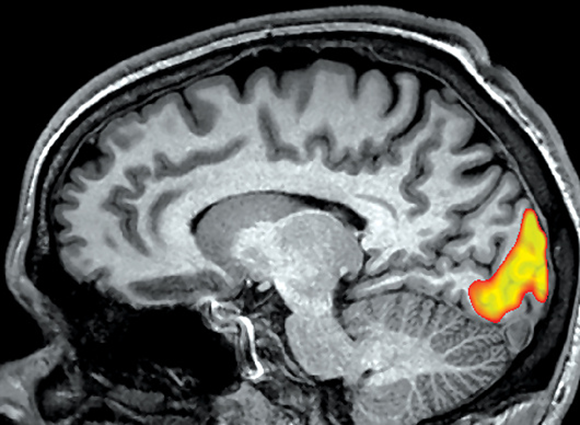

השיטה היא כיום כלי מחקרי מרכזי במדעי המוח. תמונת fMRI של מוח במצב מנוחה | Mark And Mary Stevens Neuroimaging And Informatics Institute / Science Photo Library

עבור כל ווקסל נרצה לבחון אם היה שינוי באות בזמן ביצוע המטלה, לעומת רמת האות שנמדדה בתנאי הביקורת. מוח ועליו מסומנים ווקסלים שמעלים את פעילותם (בגוונים חמים) ואלו שמורידים את פעילותם (בגוונים קרים) כאשר נבדקים הזדהו עם רגשות של אחרים | התמונה באדיבות ד”ר עדי יניב